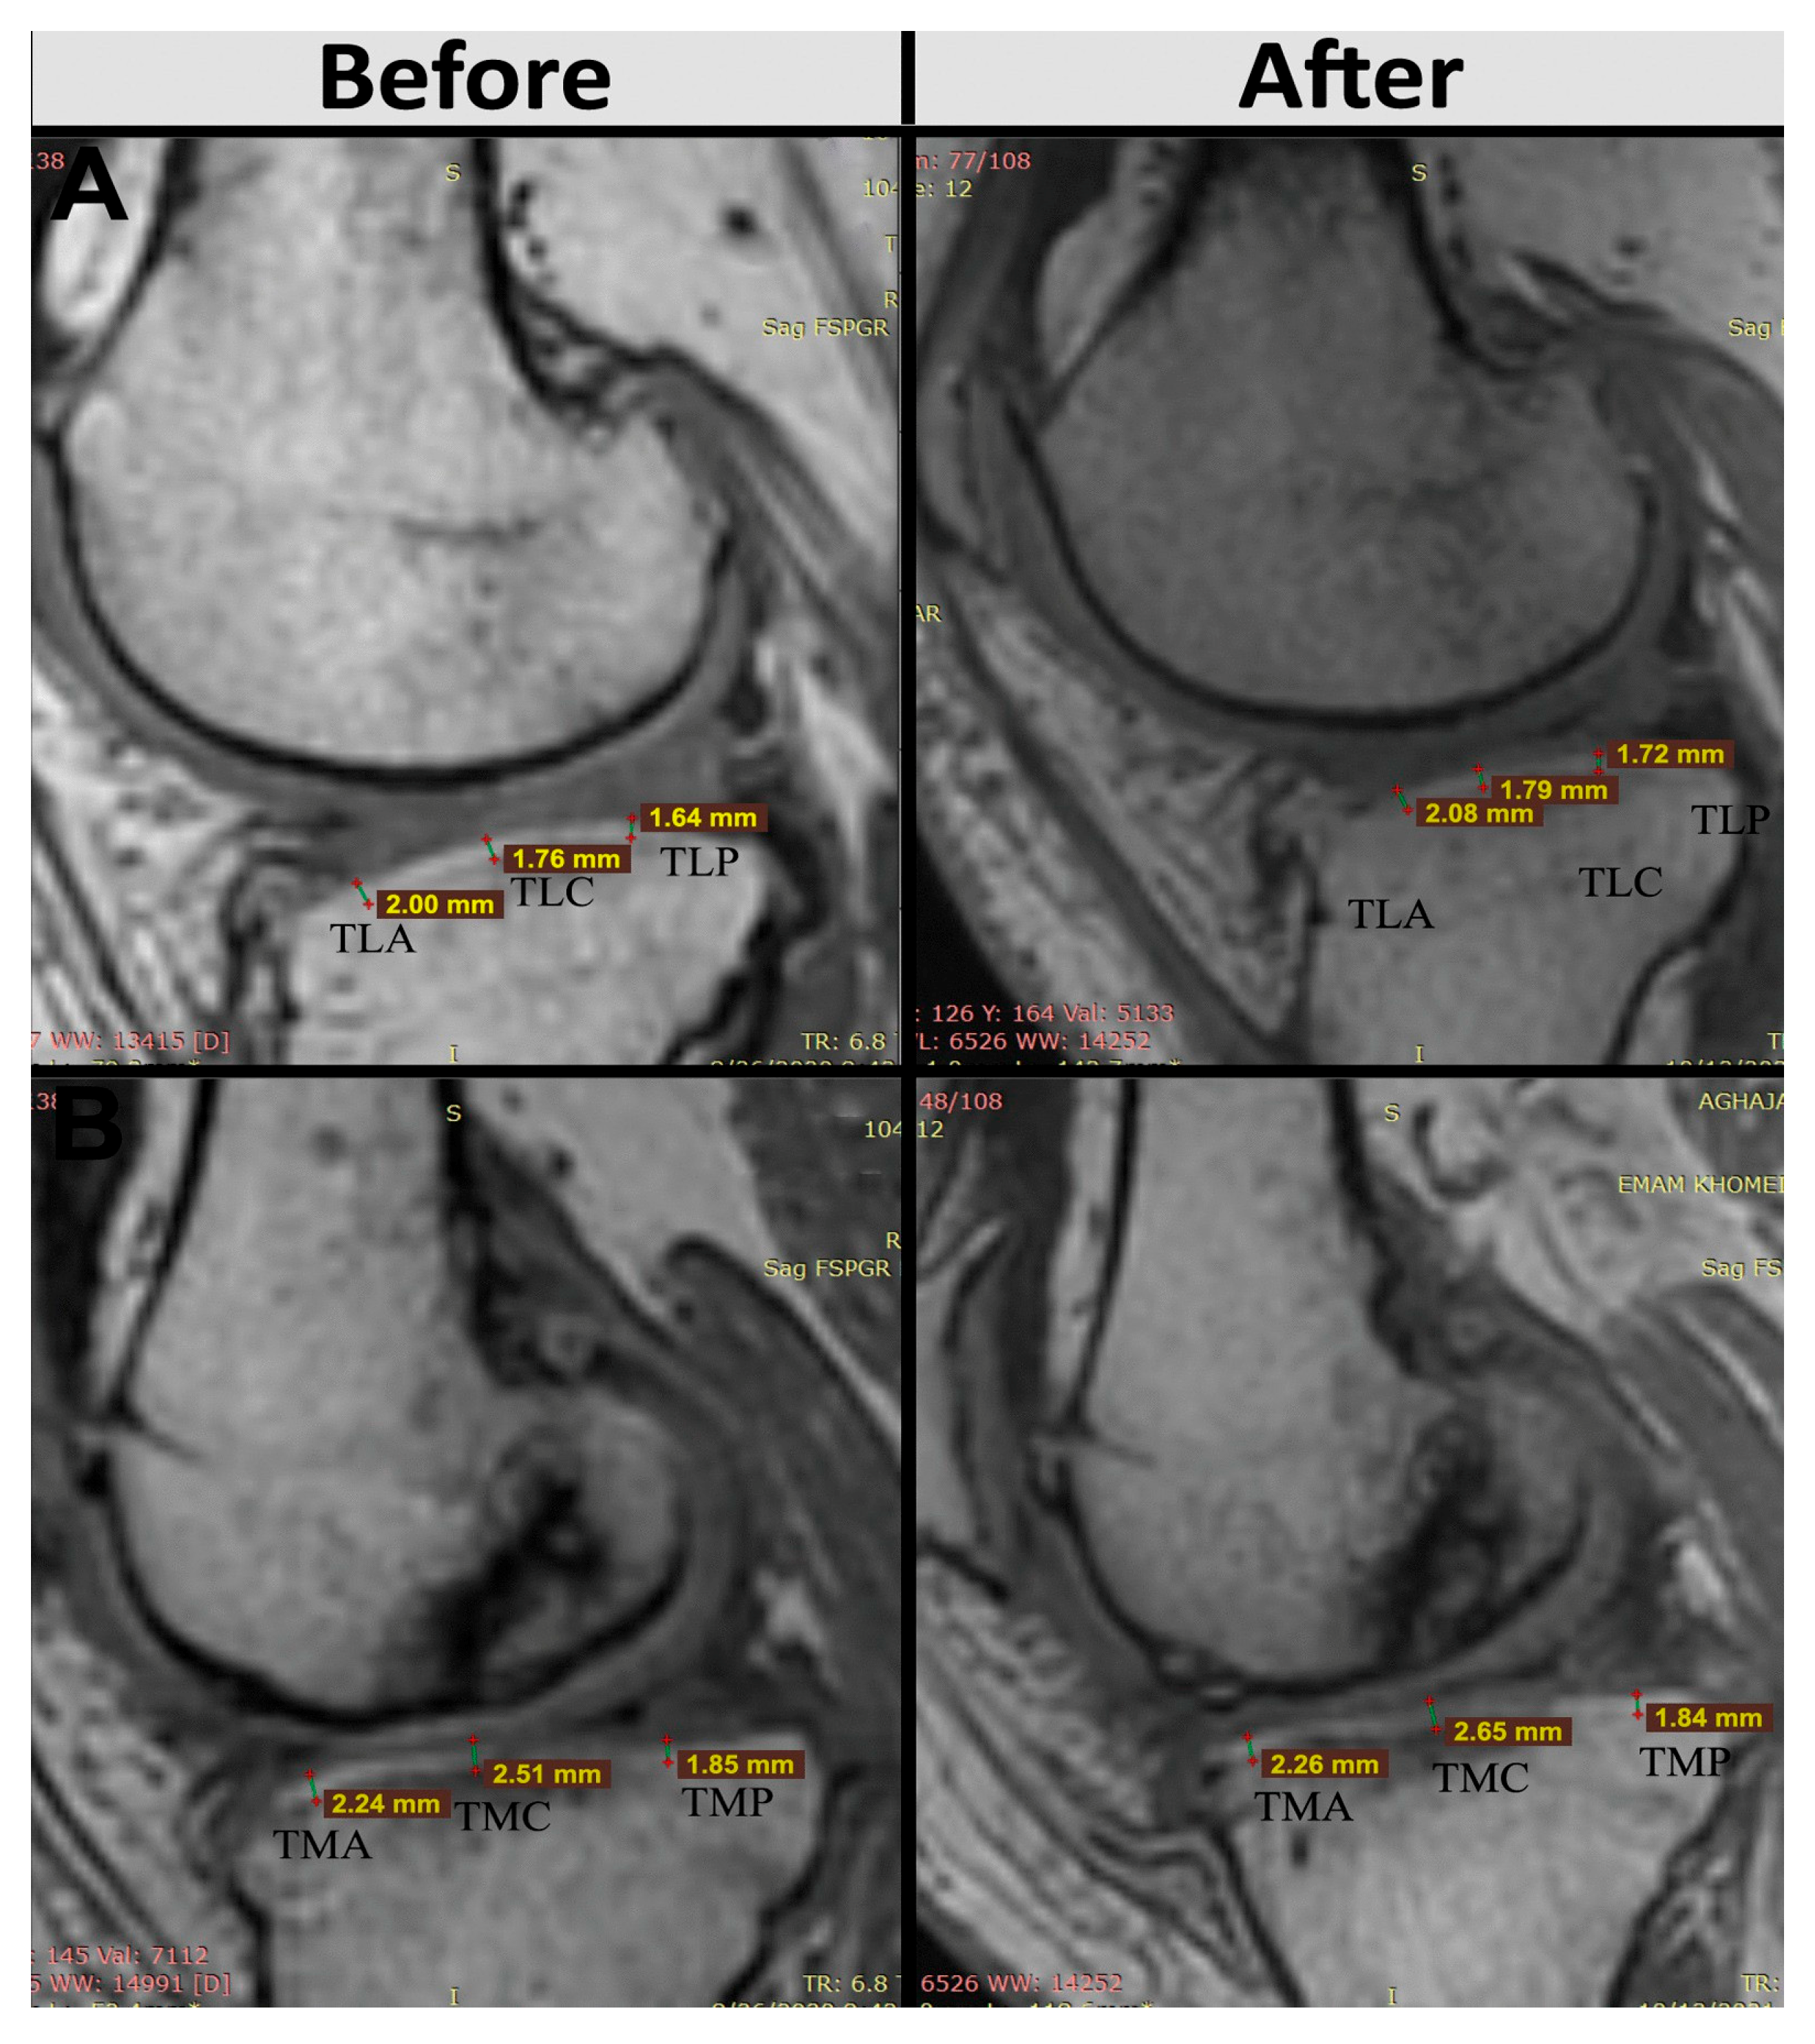

In addition to these clinical improvements, structural changes in articular cartilage thickness were objectively assessed at predefined anatomical landmarks on the tibia and femur. Patients treated with AASCs exhibited increased cartilage thickness in the medial anterior tibial region (TMA), rising from 1.86 ± 0.53 mm to 1.98 ± 0.56 mm at 12 months, and in the medial posterior tibial region (TMP), which increased from 2.01 ± 0.29 mm to 2.07 ± 0.26 mm. Conversely, placebo recipients experienced a reduction in TMA cartilage thickness, dropping from 1.49 ± 0.88 mm to 1.37 ± 0.81 mm, with TMP thickness remaining essentially unchanged (1.81 ± 0.25 mm to 1.78 ± 0.18 mm) (Figure 15).

These combined clinical and imaging findings clearly illustrate the therapeutic potential of AASCs for improving both symptomatic and structural outcomes in patients.